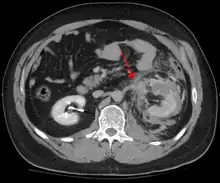

In most settings, the initial evaluation and stabilization of traumatic injury follows the same general principles of identifying and treating immediately life-threatening injuries. In the US, the American College of Surgeons publishes the Advanced Trauma Life Support guidelines, which provide a step-by-step approach to the initial assessment, stabilization, diagnostic reasoning, and treatment of traumatic injuries that codifies this general principle.[9] The assessment typically begins by ensuring that the subject's airway is open and competent, that breathing is unlabored, and that circulation—i.e. pulses that can be felt—is present. This is sometimes described as the "A, B, C's"—Airway, Breathing, and Circulation—and is the first step in any resuscitation or triage. Then, the history of the accident or injury is amplified with any medical, dietary (timing of last oral intake) and past history, from whatever sources such as family, friends, previous treating physicians that might be available. This method is sometimes given the mnemonic "SAMPLE". The amount of time spent on diagnosis should be minimized and expedited by a combination of clinical assessment and appropriate use of technology,[32] such as diagnostic peritoneal lavage (DPL), or bedside ultrasound examination (FAST)[33] before proceeding to laparotomy if required. If time and the patient's stability permits, CT examination may be carried out if available.[34] Its advantages include superior definition of the injury, leading to grading of the injury and sometimes the confidence to avoid or postpone surgery. Its disadvantages include the time taken to acquire images, although this gets shorter with each generation of scanners, and the removal of the patient from the immediate view of the emergency or surgical staff. Many providers use the aid of an algorithm such as the ATLS guidelines to determine which images to obtain following the initial assessment. These algorithms take into account the mechanism of injury, physical examination, and patient's vital signs to determine whether patients should have imaging or proceed directly to surgery.[9]